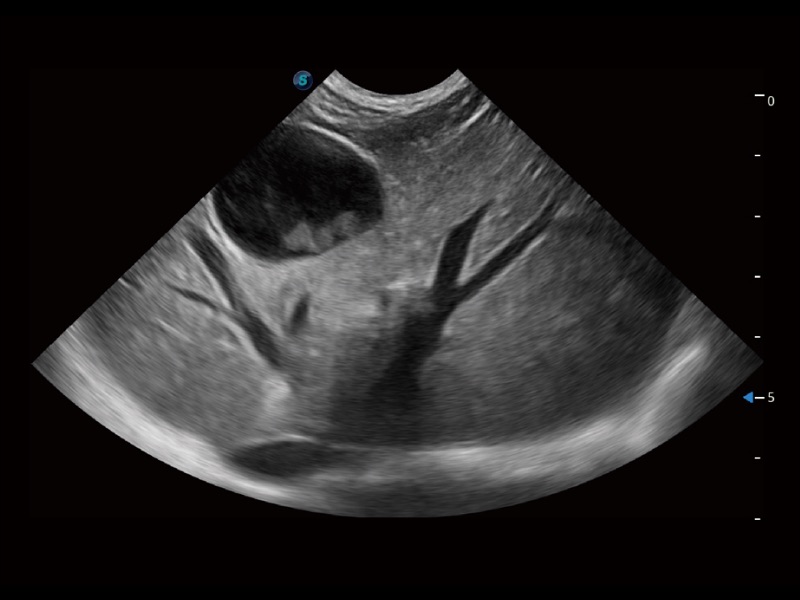

• Auto Bladder 膀胱自动测量

一键自动识别膀胱壁及自动测量膀胱容积,不受膀胱形状和大小的限制,帮助医生快速精准获得测量的数据。

(猫)胆囊

(猫)肺动脉血流频谱